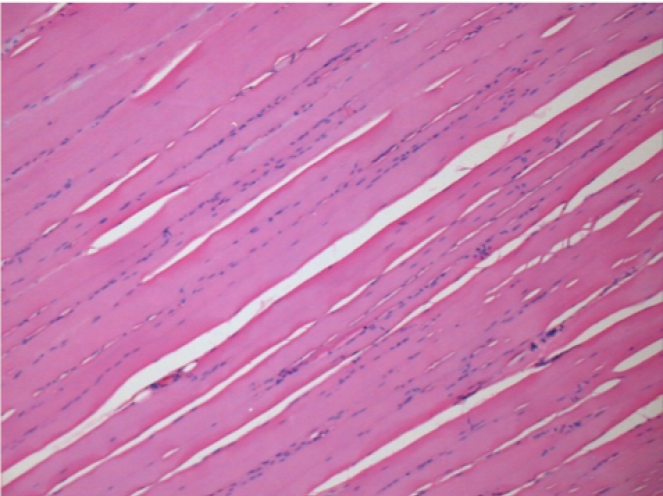

بعد شهر من حقن إندوبيل

بعد شهر واحد من حقن Endopeel 0.1 مل في العضلة أمام الظنبوب اليمنى.

ما يظهر باللون الأسود في الصور ليس نخرًا كما يتصور بعض العلماء!

في الواقع ، يجب أخذ 4 استنتاجات في الاعتبار :

- قطعة أثرية من التلوين

- عدم وجود نخر

- عملية بيولوجية

- موت الخلايا المبرمج

L : Control-100xD30

R:100xD30

R :400xD30